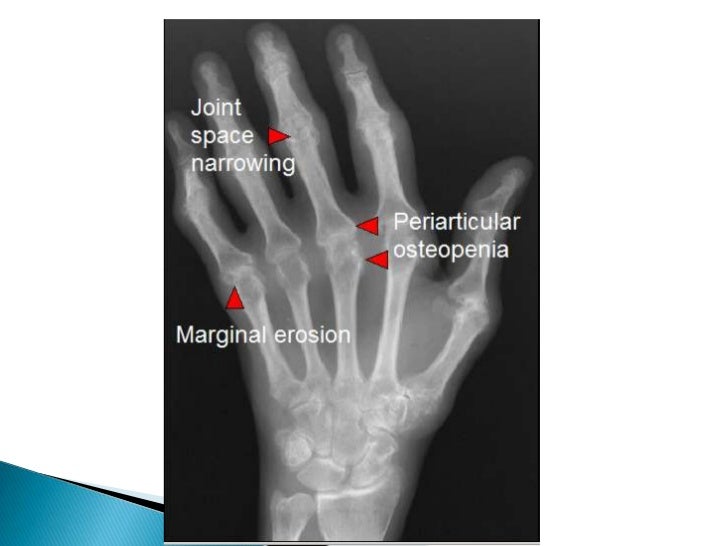

RADIOLOGI ARTRITIS REUMATOID

RADIOLOGI ARTRITIS REUMATOID documents.tips

reumatoid artritis radiologi

radiologi reumatoid artritis

RHEUMATOID ARTHRITIS – Radiologi.id

RHEUMATOID ARTHRITIS – radiologi.id radiologi.id

arthritis rheumatoid radiologi deformity radiological boutonniere mri

arthritis rheumatoid radiologi deformity radiological gambaran joints